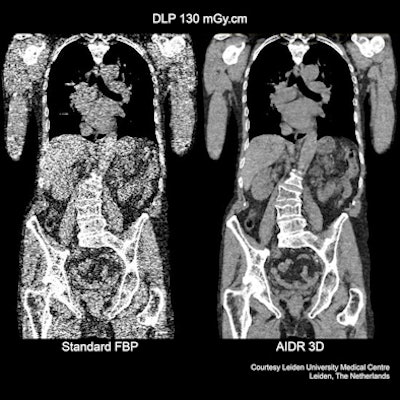

| Comparison of Toshiba's AIDR 3D and conventional filtered back projection view of the torso. |

Manufacturers of CT technology face a continuous challenge in setting themselves ever more stringent targets for reducing exposure to potentially harmful radiation. At ECR 2012, Toshiba Medical Systems Europe is introducing two new series of CT scanners incorporating its latest dose reduction technology, AIDR 3D. This Adaptive Iterative Dose Reduction software will be a standard feature on its RXL series, and will be available in a 16 and 32 slice configuration. On its CXL series, it will be available in a 64 and 128 slice configuration. The company has also announced a comprehensive upgrade scheme covering the entire European installed base of Aquilion One, Premium and Prime scanners.

Iterative-based dose reduction software requires extensive computational power, which often results in much longer reconstruction times that limit its clinical usage, especially in those examinations requiring a fast diagnosis. However, the company believes that through a combination of powerful hardware and its new AIDR 3D software its new technology will greatly extend the clinical utility of this approach.

"AIDR 3D is fully integrated in scan protocols for improved workflow, assuring a dose reduction in a clinical setting by up to 75%," noted Henk Zomer, CT business unit manager for Toshiba in Europe. "It offers a substantial noise reduction and improved spatial resolution. We also believe that this is unique software in that produces minimal penalties in reconstruction times, while assuring the best diagnostic image quality at the lowest dose for all patients. AIDR 3D works both in the image and raw data domain and is fully integrated in the exposure control for optimized dose control in all clinical settings, even in emergency departments."

The new system aims to provide benefits in terms of its diagnostic performance, which Toshiba plans to demonstrate at is exhibition stand. Since the software is adaptive, special operator handling is not needed. Automatically optimized iterations assure best image quality for each particular body region, according to Zomer.